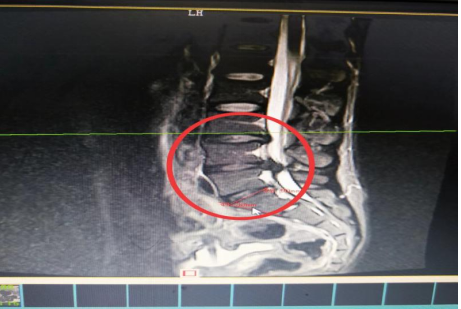

10分鐘后,患者肖先生沒有家屬陪同的情況下被緊急到骨科一區(qū)病房。接診滿頭大汗、非常緊張肖先生,舒小林醫(yī)師仔細(xì)詢問了病情。原來肖先生從事搬運(yùn)行業(yè),半年前就腰腿痛就醫(yī)當(dāng)時(shí)在保守治療后稍有緩解,沒有引起重視。直到11月13日下午因搬重物后突然感到腰腿劇烈疼痛、麻木、大小便困難,這才120急救電話。骨科一區(qū)錢軍副主任舒小林醫(yī)師立即給患者作了詳細(xì)的體查,并立即聯(lián)系做急診腰椎磁共振確定有無神經(jīng)受壓。腰椎磁共振結(jié)果提示:腰4/腰5椎間盤膨出,導(dǎo)致馬尾神經(jīng)嚴(yán)重受壓,有明顯的手術(shù)指征,如不盡快手術(shù)會(huì)致神經(jīng)受損難以恢復(fù)。錢軍副主任來到肖先生病床前,將手術(shù)方案、手術(shù)風(fēng)險(xiǎn)及并發(fā)癥詳細(xì)告知肖先生本人,肖先生表示同意并簽字馬上手術(shù)。